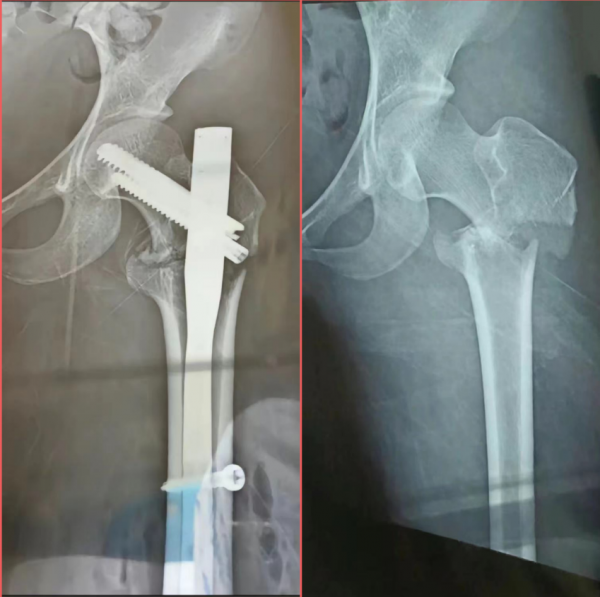

并且,女孩也将受伤时候在医院拍摄的X光片发布到网络!